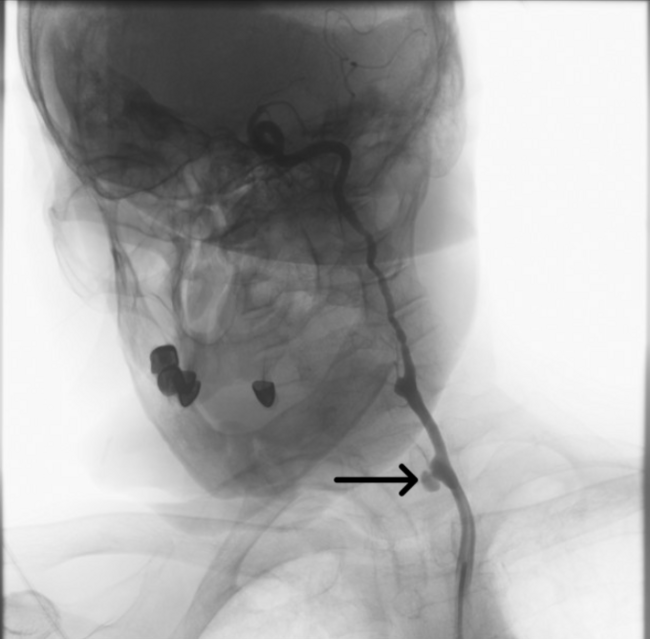

The bleeding segment was selectively wired. A 5 × 40-mm covered stent graft was deployed across the ruptured segment (Figure 2, Video 2); initial deployment was complicated by proximal slippage but hemostasis was ultimately achieved. The stent was then post-dilated with a 7 × 20-mm balloon to optimize apposition (Figure 3, Video 3). Final angiography confirmed complete sealing of the rupture and restoration of antegrade carotid flow (Figure 4, Videos 4 and 5).